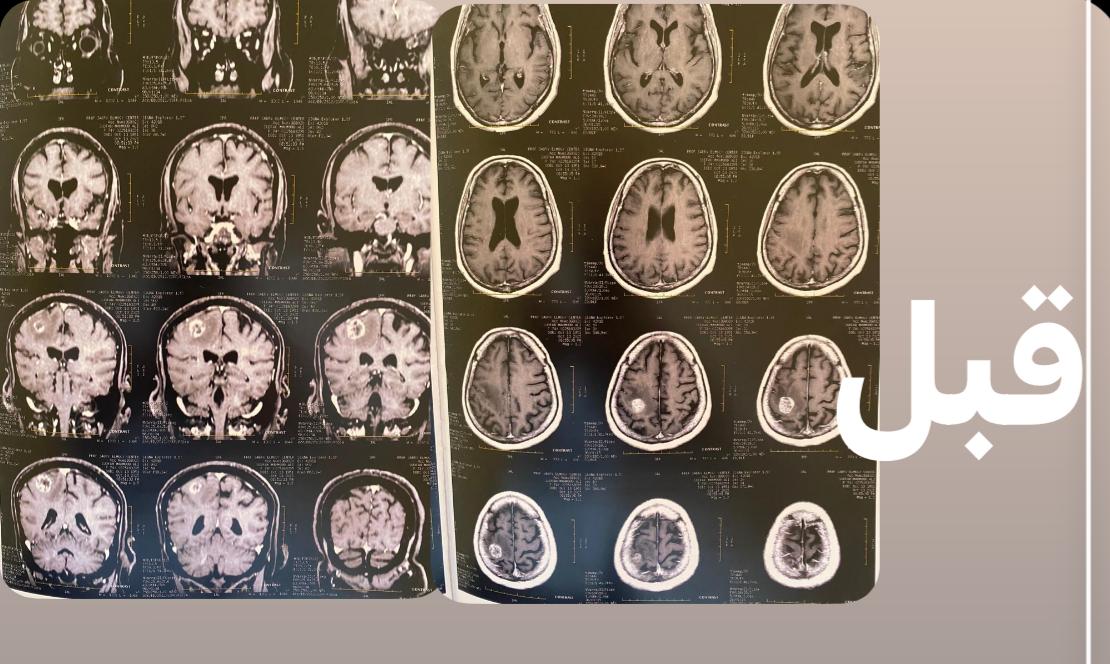

بعد إجراء الفحوصات والأشعات التشخيصية اللازمة، تم الكشف عن وجود ورم كبير في الفص الأيمن من المخ، مما أثر مباشرة على مركز الحركة وسبب تلك الأعراض المعقدة.

الدكتور السيد فاروق، وكيل الطب العلاجي، أوضح أن الفريق الطبي نجح بفضل الله ثم بالخبرات المتوفرة في إزالة الورم بالكامل عبر جراحة دقيقة، مؤكداً أن العملية تمت داخل المستشفى وسط إجراءات رعاية طبية مدروسة.

وأضاف أن السيدة استعادت وعيها التام بعد الجراحة، مع توقف التشنجات وتحسن واضح في حالتها الصحية، وهي الآن في مرحلة العلاج الطبيعي والدوائي لاستعادة كامل وظائفها الحركية.